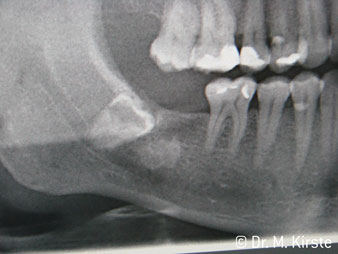

Die Winkelwahl des 45° Handstücks bringt viele Vorteile in der Anwendung. Chirurgisch tätige Kollegen, und für diese ist das Handstück in erster Linie entwickelt worden, werden schnell bemerken, dass man sehr gezielt arbeiten kann. Insbesondere bei der Weisheitszahnentfernung (Abb. 2) bedarf es keiner großen Weichteilabspreizungen im Wangenbereich (Abb. 3). Die Handstückkopfgestaltung kombiniert mit leichten Kopfdrehungen bei der Präparation lassen ein sicheres und schnelles Arbeiten im retromolaren Bereich zu.

Die professionelle Lagergestaltung im Innenleben des Handstückkopfes garantiert einen ruhigen Lauf der Bohrer, bei der Zahn- oder Wurzelseparation (Abb. 4 - 9) zeigt sich ein beeindruckendes Schnittbild ohne Schlageffekte.